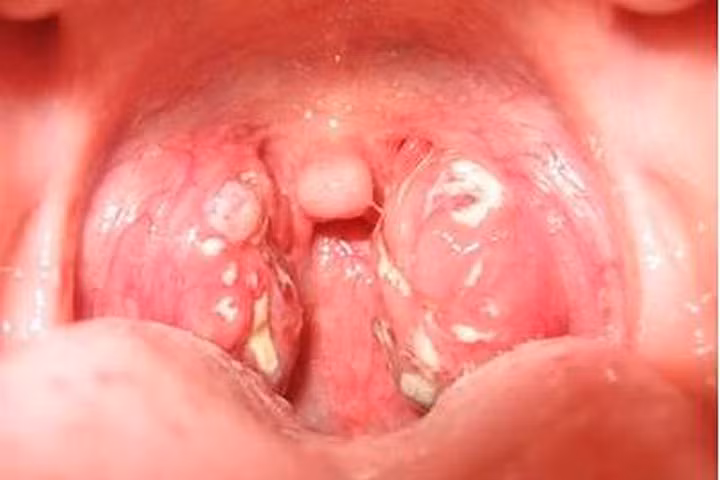

Khi quan sát bên trong họng sẽ thấy niêm mạc họng đỏ, dày, ướt, có những hạt trắng ở thành sau họng. Các triệu chứng trên sẽ tiến triển hơn ở những người hay uống rượu, hút thuốc lá, công việc phải nói nhiều. Khi sức đề kháng của cơ thể bị giảm sút, làm việc căng thẳng, bệnh có thể nặng lên thành một đợt viêm họng cấp.